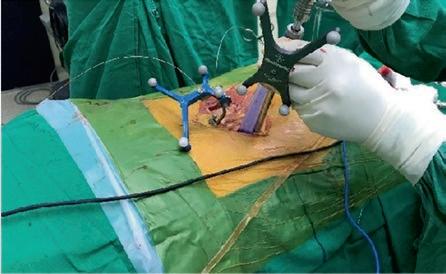

在过去的十年中,TLIF(经椎间孔腰椎椎体间融合)已经成为实现节段性椎体间融合的流行技术。最小通路技术的最新进展有助于通过微创方法进行手术,并提供充分的减压和固体融合。微创技术也有助于避免传统的后路开放入路[1,2]的许多缺点。Schwender等人[3]的一项研究报告了在接受微创TLIF手术的患者的视觉模拟评分和奥斯威特残疾指数评分有临床显著改善,100%的融合率为100%。在MIS病例中,通过更小更窄的解剖进行可视化。退行性脊柱侧弯存在复杂的脊柱病理,如脊柱旋转、透视镜解剖不良、椎弓根不对称和形状异常的椎弓根,可对MIS-TLIF构成严重挑战,导致椎弓根螺钉和钛笼[4]放置不正确。脊柱手术中的图像引导导航对MIS外科医生是一个宝贵的帮助,因为它允许更大的区域。透视可以帮助螺钉放置;然而,它增加了手术时间和辐射暴露给外科医生和手术室人员。据报道,徒手和透视引导下椎弓根螺钉置入时,腰椎移位率高达30%,胸椎移位率高达50%。mal定位的螺钉可能对脊髓、神经根和大血管造成潜在的损伤,也会降低脱位的稳定性。医学法律上对患者安全的担忧进一步加强了图像引导螺钉放置的必要性,以提高[5]的准确性。

计算机辅助脊柱手术(CASS)是一门使用新的基于计算机的技术的学科,包括立体定向、导航手术和机器人技术。导航辅助脊柱手术是一组技术,它允许外科医生在手术中获取与手术器械相关的实时、三维和虚拟的脊柱图像。